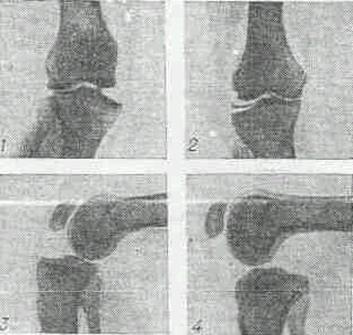

Рис 5 Рентгенограмма коленного сустава при различных повреждениях коленного сустава

1 - разрыв большеберцовой коллатеральной связки - отклонение голени к наружи;

2 - разрыв малоберцовой коллатеральной связки - отклонение голени кнутри при нагрузке;

3 - повреждение передней крестообразной связки, патологическое увеличение выдвижение голени кпереди ("симптом переднего выдвинутого ящика");

4 - повреждение (разрыв) задней крестообразной связки, патологическое увеличение выдвижение голени кзади ("симптом заднего выдвинутого ящика").